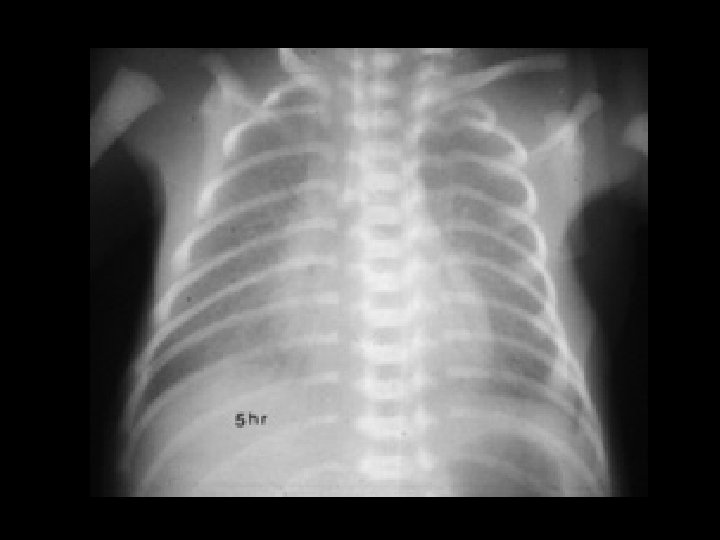

Hyaline Membrane Disease (HMD) • Findings: – symmetric, homogeneous “ground glass” appearance – air-bronchograms – decreased lung volumes • Pre-term infants with sufactant deficiency • generalized capillary leak • ddx: – neonatal pneumonia – transient tachypnea of the newborn – meconium aspiration